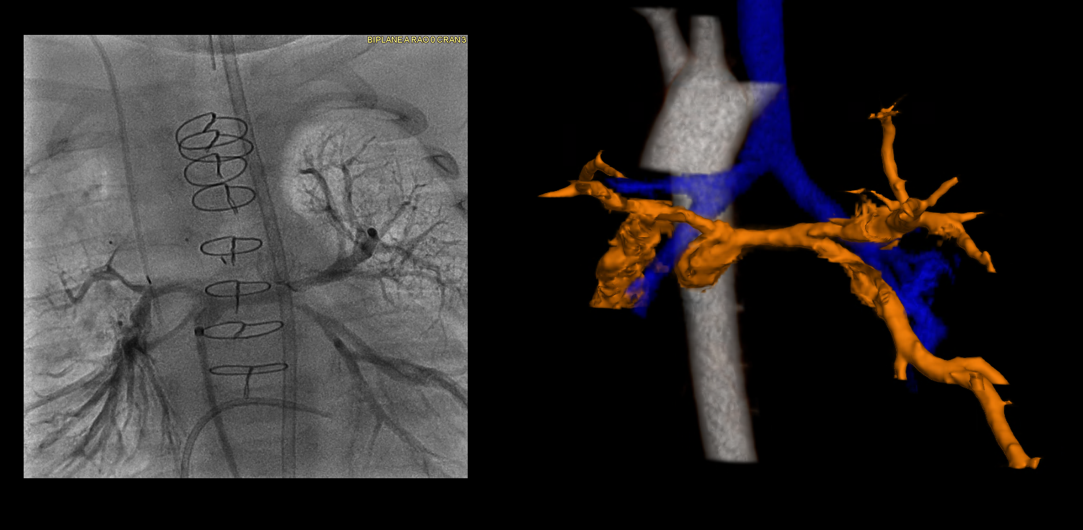

We use our deep experience and expertise to evaluate your child’s condition with the most advanced imaging tools available. We create a 3D map of the heart anatomy.

- Cardiac CT with 3D reconstructions. Data from a computed tomography scan creates a visual model of the heart anatomy.

- Cardiac catheterization. An interventional cardiologist inserts a thin tube with a tiny camera through a blood vessel in the groin or arm and guides it to the heart. This shows images of the heart structures, vessels and any blockages.

Our advanced imaging techniques clearly define the anatomical details of the major aortopulmonary collaterals and any existing heart anomalies.

We use 3D and virtual reality models to predict procedure outcomes. These tools help design the right cardiac catheterization interventions and the best surgical approach.